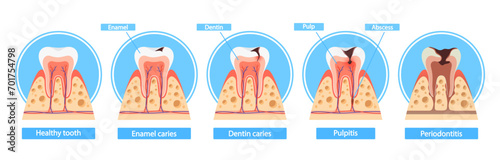

- Naučné plakáty pro školy

- Lékaři